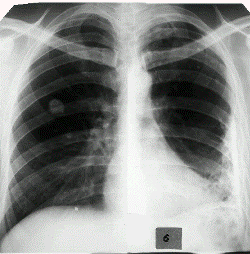

Симптомы и лечение плеврита народными средствамиПлевральный выпот – это избыточное скопление жидкости в плевральной полости, которое может возникнуть из-за воспаления  плевральных листков, а кроме того нарушением кровообращения, лимфообращения, увеличением проницаемости капилляров невоспалительной причины, онкологией плевры или прочими причинами. Плеврит – это воспалительный процесс в плевре (наружной мембране, покрывающей легкие), с появлением фиброзного налета на ее поверхности и наличием выпота в полости.

Плеврит может быть вызван инфекцией, развитием опухоли или травматическим повреждением груди.